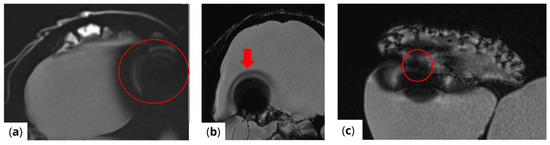

RF pulse inhomogeneity can arise due to coil design and signal reception inconsistencies, leading to unwanted spatial signal variations within the image. Differences in local RF flip angles depend on both scanner calibration and RF energy distribution. One disadvantage of high-field MRI (3 T and above) is increased image inhomogeneity caused by RF wave interference within the scanned volume. At higher frequencies, the RF wavelength becomes comparable to the size of scanned structures (e.g., tissues or materials), leading to destructive interference, signal loss in some areas, and signal amplification in others. This effect is clearly visible (Figure 4) in the t1_vibe_fs_tra sequence and t2_tse_fs_tra sequence.

Figure 4.

Effects of RF pulse inhomogeneity and high-field interference on signal distribution (a) t1_vibe_fs_tra sequence showing pronounced destructive RF interference and signal dropout, indicated by the red arrow (b) t2_tse_fs_tra sequence illustrating spatial signal amplification and central inhomogeneity.